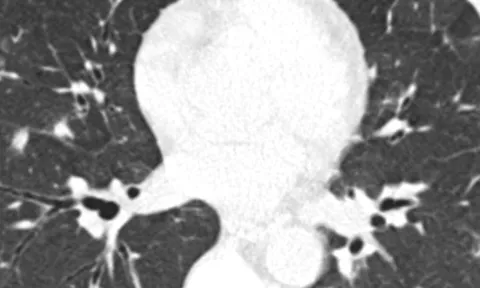

Cân não cứu sống bệnh nhân ung thư thận hiếm gặp

Đại diện Bệnh viện Bình Dân (Tp.HCM) cho biết, vừa cứu sống bệnh nhân ung thư thận có tiên lượng tử vong 90%.